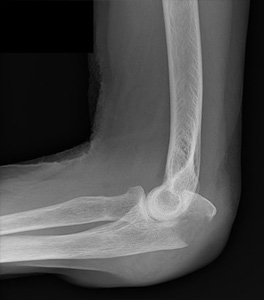

Fracture de la palette humérale

Une ostéosynthèse stable par plaques est souvent nécessaire. Le montage doit être stable pour permettre la rééducation immédiate afin de lutter contre l’enraidissement articulaire.

Fracture de la tête radiale

le traitement diffère selon les stades, en fonction du déplacement et du nombre de fragment.

On distingue le traitement fonctionnel pour les fractures peu déplacées : écharpe coude au corps à visée antalgique à 10 jours et mobilisation précoce du coude.

Et le traitement chirurgical pour les fractures déplacées : ostéosynthèse par vis enfouies, plaque ; ou remplacement de la tête radiale par une prothèse dans les cas où la tête radiale n’est pas réparable.

Fracture de l’olécrane

En plus de la fracture articulaire, la fracture de l’olécrane correspond à une interruption de l’appareil extenseur du coude. Les fractures déplacées nécessitent une ostéosynthèse adaptée à la fracture : par broches et hauban, par ostéo suture ou par plaque vissée en fonction de l’âge, de la qualité osseuse et de la taille des fragments.